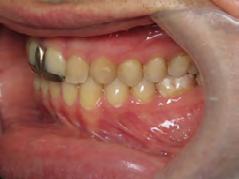

Approximately six months after insertion of the RPE, digital scans were taken for SureSmile custom wires and the patient was scheduled for the SFOT procedure with the oral surgeon. The RPE was removed, SureSmile wires inserted and segmental corticotomies performed, immediately followed by further vertical elastics on the right side (Figure

4). Archwires were upgraded incrementally into 19 x 25 SS. Once the bite was completely closed, the patient was referred to the myofunctional therapist to begin treatment. Eight sessions of myofunctional exercises were performed, focusing on muscle building, toning, synchronicity and awareness. Improvement in correct chewing, swallowing and resting postures of the lip and tongue were addressed. All appliances were removed 21 months after initial insertion (Figure 5), and the patient was referred to a re-

Figure 4. Post-corticotomy, with SureSmile custom wires.

The patient finished with Class I occlusion, ideal overbite and overjet. The arches are co-

Figure 5. Final records.

ordinated, lateral open bite closed and occlusal cants leveled. From the frontal cephalometric tracings, maxillary width increased from 58 mm to 69 mm. From the lateral cephalometric tracing, the incisor angulations remained unchanged. The final report from the myofunctional therapist indicated the patient eliminated the bilateral posterior tongue-thrust swallowing pattern with saliva, liquid and solid swallows. Correct swallowing mechanics were demonstrated while sipping/gulping liquids from a cup. His day and nighttime tongue-resting postures were reported to be on his incisive papilla, with lateral margins lightly suctioned into the upper arch. Lips were closed and competent diurnally and nocturnally.

Most recent records are two years after removal of the orthodontic appliances, demonstrating the stability of the results (Figure 7).